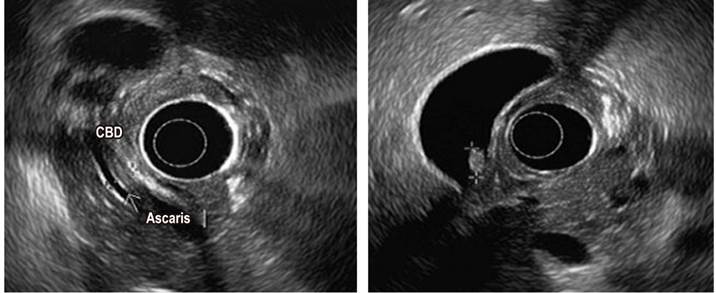

An abdominal ultrasound was performed as a complementary study, revealing a gallbladder polyp and biliary sludge without alterations of the bile duct. Endoscopic ultrasonography was performed due to the intermediate risk of choledocholithiasis associated with an increase in bilirubin levels, alteration of the liver panel, clinical symptoms of biliary pancreatitis (Table 1), and greater sensitivity for microlithiasis. Imaging manifestations of cholelithiasis were observed, which were consistent with AL in the choledochal lumen, with an elongated hyperechogenic tubular structure that did not produce acoustic shadowing and railway track sign (Figure 2). Albendazole treatment was prescribed (400 mg orally, every 24 h for 3 days) and an ERCP was performed, along with papillotomy and removal of ascaris from the biliary tract. There were no postoperative complications (Figure 3).

Figure 2 Pancreatobiliary endoscopic ultrasonography: cholelithiasis, biliary ascariasis. CBD: Common bile duct. Source: Own elaboration.